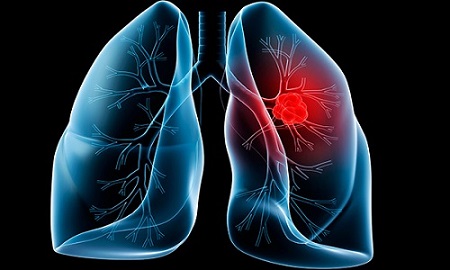

Các yếu tố chủ yếu dẫn đến ung thư phổi?

Thuốc lá, thuốc lào: 90% bệnh nhân ung thư phổi là do nguyên nhân này. Tuy nhiên, không chỉ những người hút thuốc mới mắc phải, những người hít phải khói thuốc cũng có nguy cơ mắc ung thư phổi rất cao.

Ô nhiễm môi trường: môi trường làm việc, môi trường sống chứa các hóa chất độc hại như niken, silic, khí than, crom,… cũng là nguyên nhân gây ung thư phổi. Nguy cơ này sẽ thực sự đáng báo động và tăng lên gấp nhiều lần nếu người bệnh có sử dụng thuốc lá.

Tiếp xúc với tia phóng xạ: môi trường phóng xạ khiến tỷ lệ mắc ung thư, đặc biệt là ung thư phổi tăng lên rất cao.